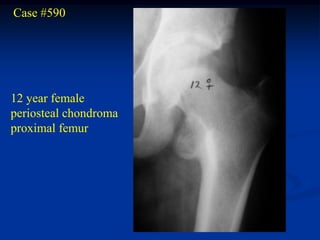

Case #590

12 year female

periosteal chondroma

proximal femur

Frog leg lateral